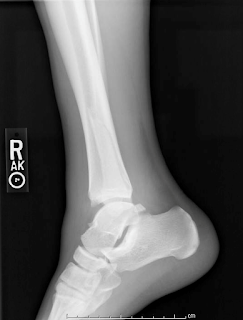

In addition to a spiral fracture of the distal diaphysis of the fibula, the patient’s imaging is concerning for a high ankle sprain given the medial displacement of the tibia, lateral displacement of the fibula, and increased tibiofibular clear space.

Below are the patient’s initial ankle radiographs. Based on the Weber ankle fracture classification, what would be the likely course of management for this patient?

The Danis-Weber classification system for ankle fractures has three major classifications for fibular fracture: Type A, B, and C. In general, the more proximal the fracture the greater risk of disruption of the syndesmotic ligaments, and thus greater associated instability.[6] Type A refers to a lateral malleolar avulsion fracture below the level of the talar dome. Type B refers to an oblique or spiral fracture of the fibula at or near the level of the syndesmosis. Evidence suggests that Type A and Type B fractures unimalleolar fractures have similar outcomes, showing lower rates of complications compared to Type C. However, other important factors inversely correlated with prognosis include the number of malleoli fractured and the age of patients.[7]

This ankle fracture would specifically be a Weber type C ankle fracture. Weber type C ankle fractures are above the level of the ankle joint with tibiofibular syndesmosis disruption and associated medial injury.[6] It is important to note that Weber type C ankle fractures may arise as proximally as the fibular neck, and thus full evaluation of the fibula (on both physical exam and on radiographs) is necessary. This fracture is unstable and usually requires referral for an orthopedic consult for open reduction and internal fixation.

Figure 3. Lateral view X-ray of ankle demonstrating a spiral fracture of the fibula above the level of the ankle joint.